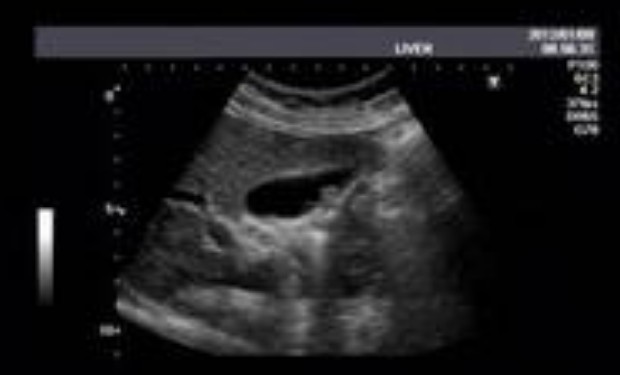

根据病史、症状、体征和B超检查,多数病人在术前可以明确诊断。但胆囊癌、胆囊腺肌病则需病理检查方能确诊。而胆囊内瘘则要靠术中的仔细探查才可以发现。胆道急性穿孔的诊断根据腹膜刺激征及B超发现胆囊壁的连续性中断,胆囊周围出现液性暗区,腹腔穿刺穿出胆汁样液体,诊断即可明确。对胆囊穿孔要进行多角度、多体位、全面的B型超声检查,基本能发现胆囊穿孔部位。即使B超未探及胆囊壁连续性中断,若在胆囊炎的基础上如有明确的胆囊周围积液,应考虑胆囊穿孔。因此必须重视B 超检查,以提高早期诊断率。胆囊慢性穿孔病人腹膜刺激征等临床表现亦不甚明显,可通过B 超声像图显示胆囊窝有一复合性囊性肿块向上蔓延侵入肝脏以及超声“孔眼征”来诊断。血白细胞升高,老年人、免疫力低下患者则可不升高,不应据此而认为没有感染。